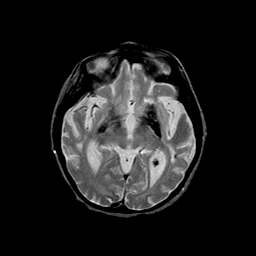

Basal Ganglia Calcification: T2-weighted MR -- Slice #8

[Home][Help][Clinical] Slice 8